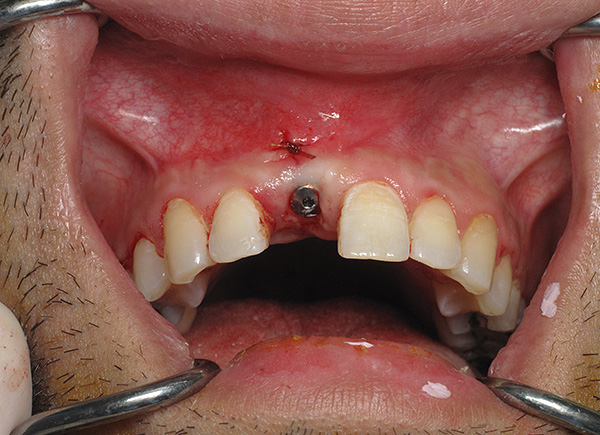

Le fotografie seguenti mostrano un esempio corrispondente (posizionamento di un impianto al posto di un dente estratto dopo la guarigione di un foro):

nota

L'impianto classico pone le massime esigenze in merito alle condizioni del tessuto osseo, quindi, dopo l'estrazione del dente, devono essere necessari circa 3-4 mesi prima di poter installare l'impianto. Il tessuto osseo deve recuperare completamente.